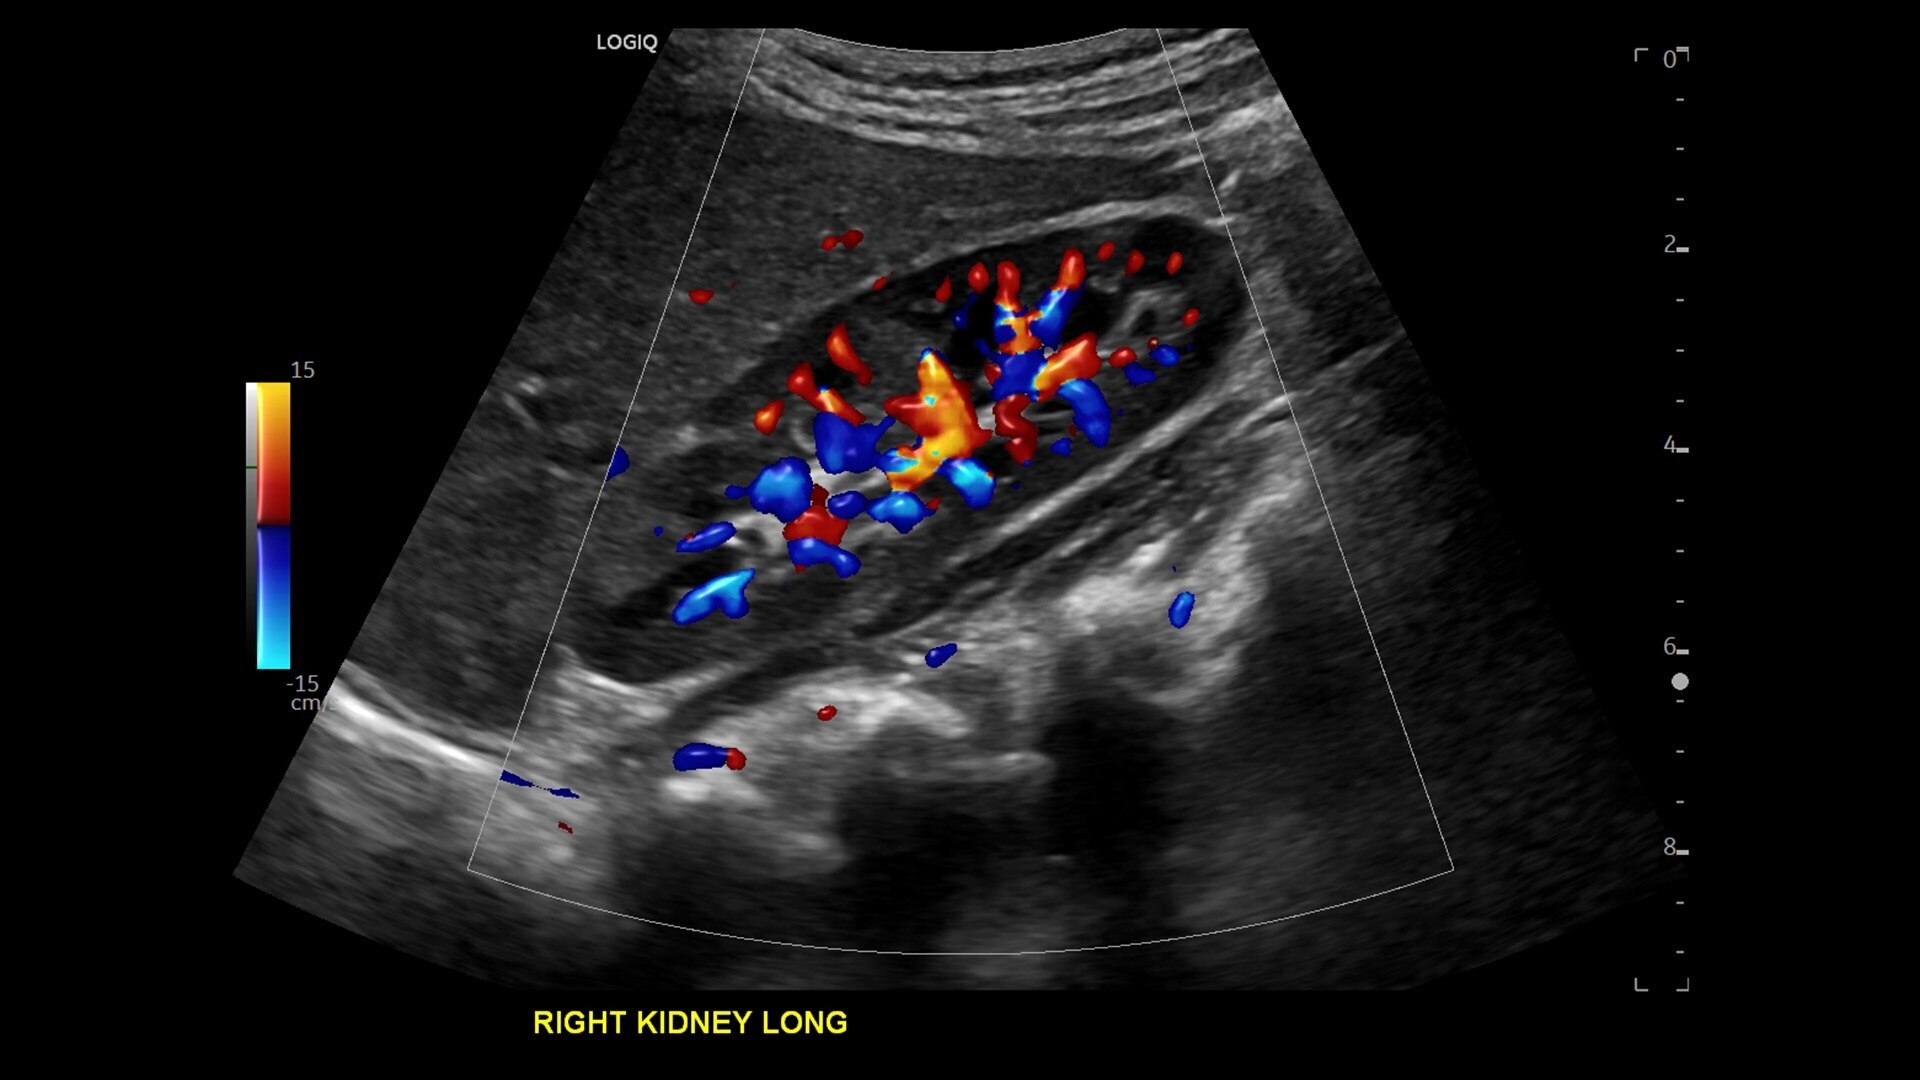

• Advanced flow modes give you the flexibility, from large vessels to fine microvascular detail, to visualize blood flow with precision

• New Auto Renal Measure Assistant: Automatically detects kidney and measures length, height and width in seconds*

• Auto Abdominal Color Assistant 1.0: Automatically detects what anatomy is being scanned and selects the correct abdominal flow shortcuts in real time